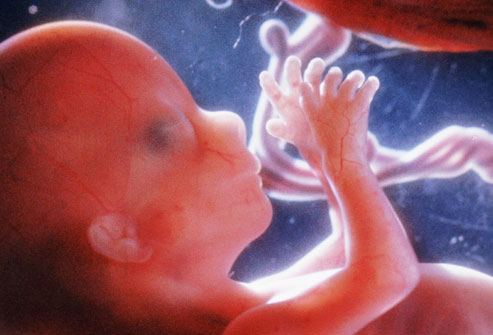

Fetus at 4 Weeks

Fetus at 8 Weeks

Fetus at 12 Weeks

Fetus at 16 Weeks

Fetus at 20 Weeks

Fetus at 24 Weeks

Fetus at 28 Weeks

Fetus at Week 36

All pictures came from:  http://www.webmd.com/baby/slideshow-fetal-development